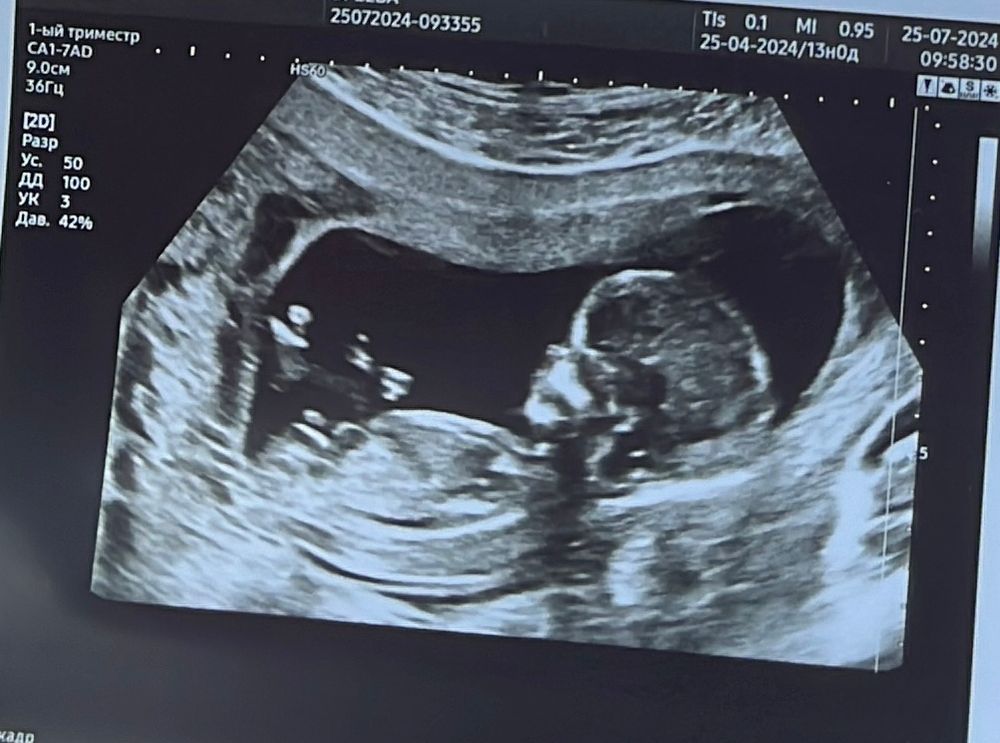

Девочки,как думаете мальчик или девочка?)

Крутовато на первом скрининге пол определять. На втором-то не все правильно ставят. Обычно кому интересно, кровь на пол сдают.

Если я правильно вижу бугорок, то это девочка)

Говорят что мальчики пузатее. У меня сошлось, сравнивала узи на таком сроке сына и дочи))) поэтому я думаю что девочка

На девочку похожа